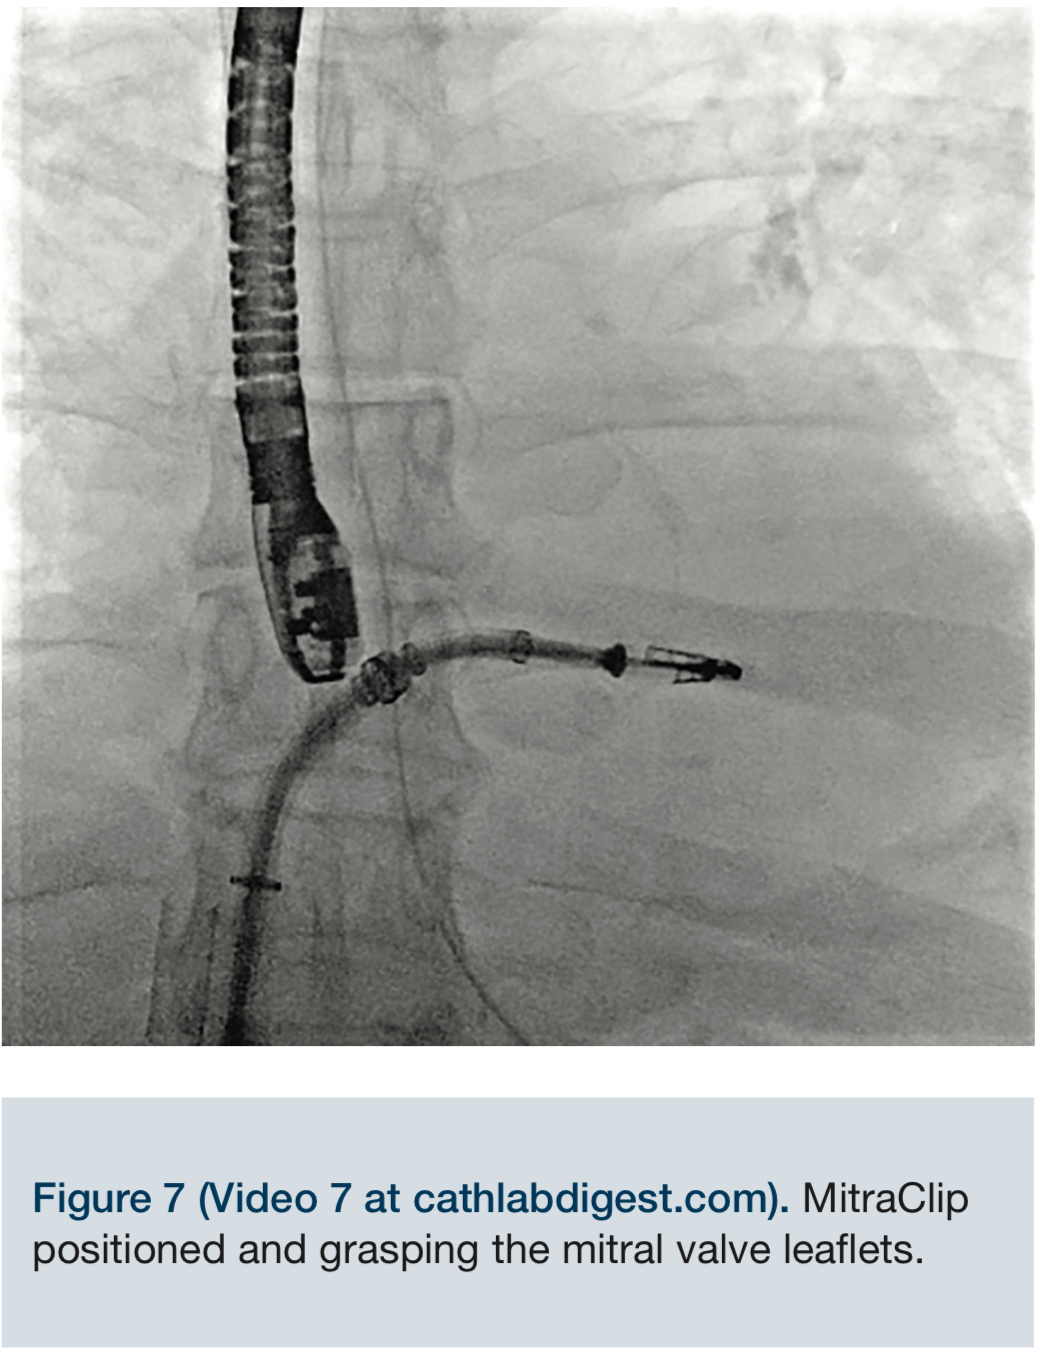

Video 7. MitraClip positioned and grasping the mitral valve leaflets.

The MitraClip delivery system was then advanced into the left atrium, and the delivery system was placed into a suitable position over the targeted area, under fluoroscopic and echocardiographic guidance. The clip was advanced into the left ventricle and retracted, trapping the leaflets. The mitral regurgitation was evaluated with the clip partially closed and found to be significantly reduced. The regurgitation was essentially eliminated, and the clip was fully closed.

The MitraClip delivery system was then advanced into the left atrium, and the delivery system was placed into a suitable position over the targeted area, under fluoroscopic and echocardiographic guidance. The clip was advanced into the left ventricle and retracted, trapping the leaflets. The mitral regurgitation was evaluated with the clip partially closed and found to be significantly reduced. The regurgitation was essentially eliminated, and the clip was fully closed.